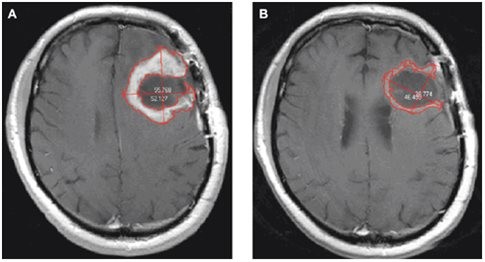

Το γλοίωμα είναι ο ιατρικός όρος για την περιγραφή των όγκων που πηγάζουν από τον κολλώδη ή υποστηρικτικό ιστό του εγκεφάλου. Πάνω από το ένα τέταρτο των καρκίνων του εγκεφάλου και το 80% των καλοηθών εγκεφαλικών όγκων είναι γλοιώματα.